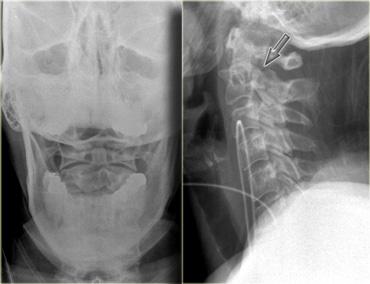

Hình bên trái là một trường hợp gãy mỏm răng loại II khác.

Đôi khi các đường gãy này có thể khó nhận thấy.

Có những hình ảnh giả gãy xương như các đường thấu quang do chồng hình (overprojection) hoặc đường Mach nổi bật (hình minh họa).